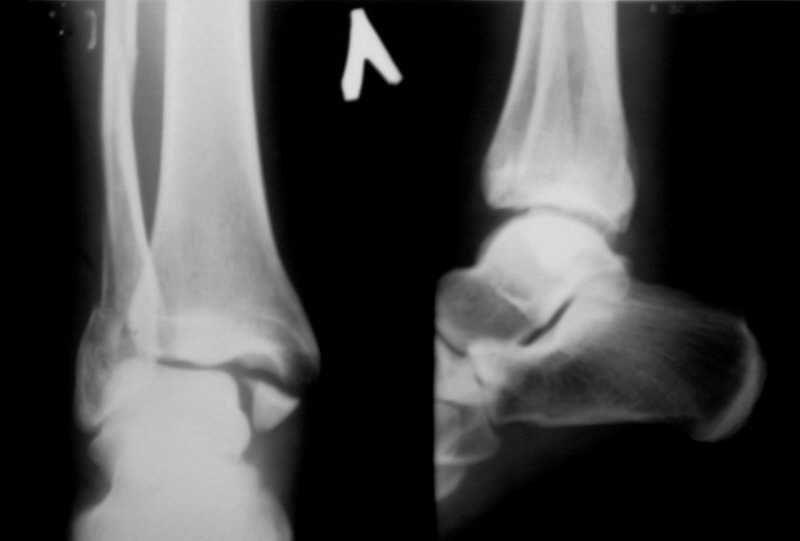

Пациентка, 30 лет с таким переломом. Произвел репозицию.

Теперь думаем, то ли так оставить, или все-таки, выполнить остеосинтез согласно рекомендациям АО? Хотелось бы услышать мнение коллег -- С ув. Sergey Melashenko